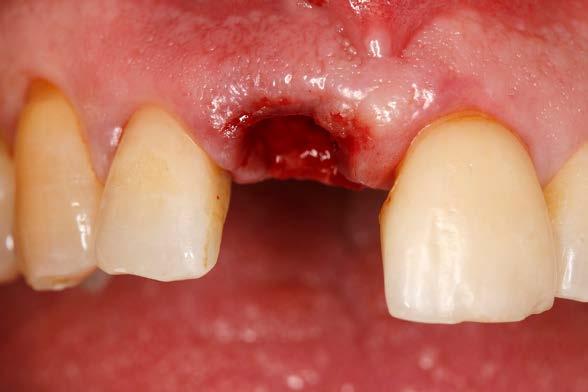

Caso clínico

Presentamos el caso de un paciente varón de 47 años, que acude a la consulta dental por presentar dolor, movilidad y fístula en la pieza dental 11. Este caso, fruto de un traumatismo previo, tuvo que ser endodonciado y posteriormente realizada sobre el mismo una apiceptomía, para abordar un quiste apical residual que no terminaba de evolucionar de forma favorable. El trabajado de rehabilitación posterior se llevó a cabo con una reconstrucción con poste y una carilla cerámica. Tras varios años, el diente ha comenzado de nuevo con los síntomas anteriormente descritos por lo que se sospecha la presencia de una fractura radicular. La

radiografía panorámica inicial para el diagnóstico nos aporta una imagen radiolucida entorno al ápice del diente en posición 11 ( Figura 1 ). Para conocer mejor el alcance de la lesión y las opciones terapéuticas de las que disponemos se lleva a cabo un cone-beam en el que se puede objetivar de forma precisa el defecto apical al diente. Este defecto es circunferencial y está dejando una reabsorción casi completa de la tabla ósea vestibular y parcial de la palatina, con un grosor de 1.9 mm, como vemos en el corte seccional (Figura 2). Si observamos la medida total en la zona media del incisivo dentral, necesitamos cubrir una anchura aproximada de 8 mm por lo que el implante que coloquemos irremediablemente dejará un gap, que según los protocolos quedará en vestibular. Utilizando una plataforma estándar de 4.1 mm el gap a rellenar será prácticamente de 4 mm según las medidas que nos

Figura 2. Corte seccional del cone-beam

arroja el cone-beam de planificación. Utilizaremos además un implante de longitud mayor que la que se emplearía para un incisivo central en una zona edéntula, para lograr un anclaje apical que nos dé la estabilidad necesaria en la colocación del implante y

nos permita la carga inmediata posterior. En este caso 11.5 mm (Figura 3 y 4).Una vez diagnosticado el caso de forma correcta con las imágenes del cone-beam iniciamos la fase quirúrgica. Realizamos la exodoncia del diente 11 con el menor trauma

Figura 3. Diámetro del alveolo tras la exodoncia del diente 11.

Figura 4. Planificación del implante de plataforma universal con una longitud que nos permita anclarnos apicalmente.